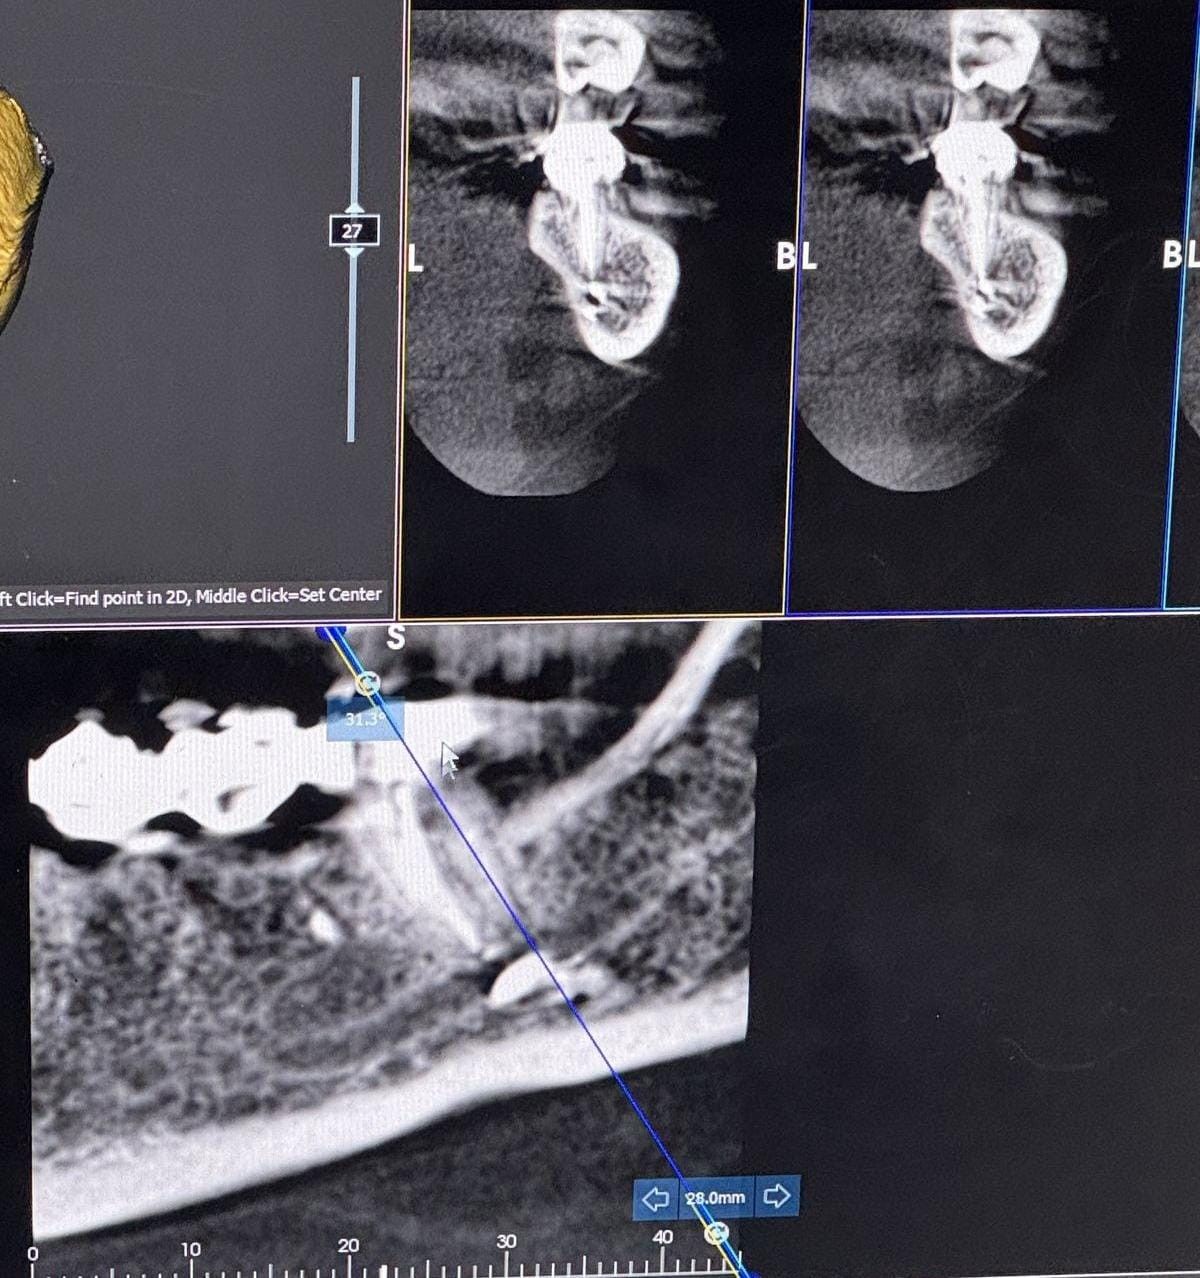

"Bütün bu müddət ərzində məsuliyyət daşıyan tərəf mənə heç bir köməklik göstərmədi. Həkim məni başqa bir həkimə yönləndirəcəyini dedi, lakin onu da etmədi. Əlimdə rentgen görüntüləri və əməliyyat sənədləri var".